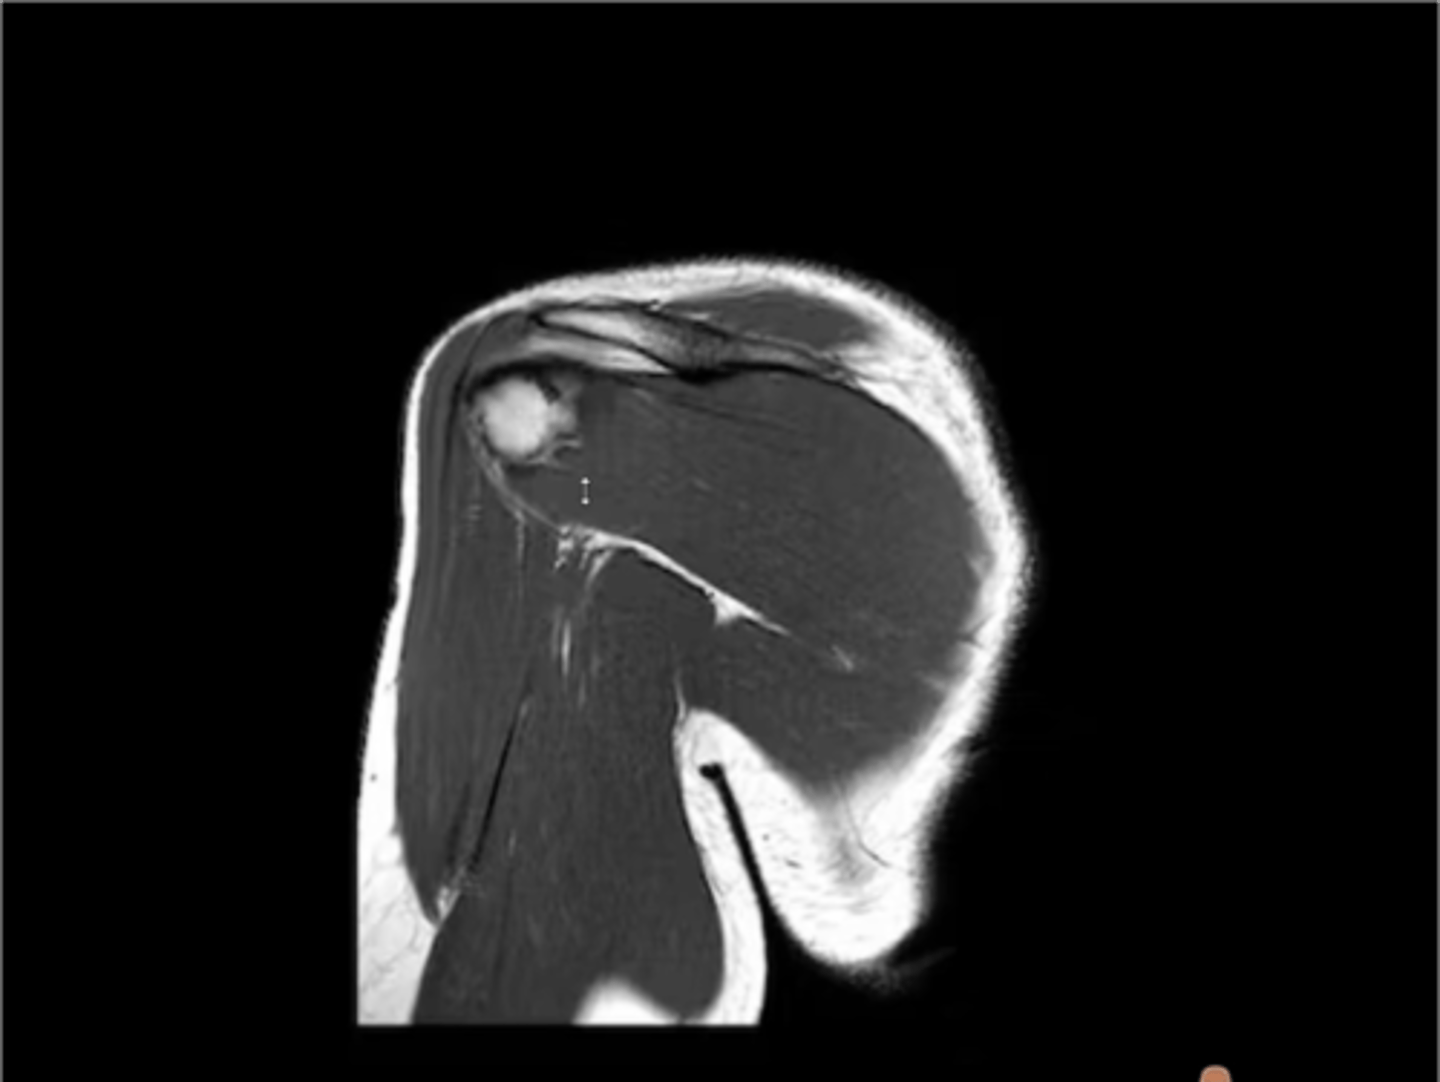

Posterior coronal view of the shoulder -- now, instead of seeing the supraspinatus, we are seeing the infraspinatus

What type of view is this? Anterior vs. posterior? How do you know?

1. Posterior coronal view

2. NO CORACOID

3. Posterior deltoid

1. What view is this image?

2. How do you know?

3. Which structure is being pointed to?

2. NO CORACOID -- spine of the scapula

3. Superior = spine of the scapula, inferior = infraspinatus

3. Which structures are being pointed to?

2. Glenoid

2. Which structure is being pointed to?

1. Upper trap (superiorly)

2. Supraspinatus (inferiorly)

Which structures are being pointed to in this image?